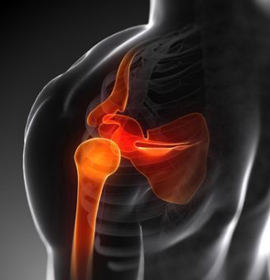

Cuando existe una lesión del hombro, el médico a menudo puede diagnosticar el problema basándose en el examen físico. Sin embargo, a veces se necesitan radiografías o resonancia magnética nuclear (RMN).

La artroscopia es una técnica quirúrgica de mínima invasión, la cual consiste en la introducción, de una camara (artroscopio) en una articulación mediante una pequeña incisión en la cual nos permite realizar una evaluación completa, un diagnóstico y al mismo tiempo realizar un tratamiento en las articulaciones. ofreciendo mejores resultados, como por ejemplo en lesiones de manguito rotador, lesiones meniscales o ligamentarias de rodilla u otras articulaciones como tobillo, brindando mayor rapidez de recuperación y reduciendo las probabilidades de complicaciones en comparación con las técnicas abiertas.